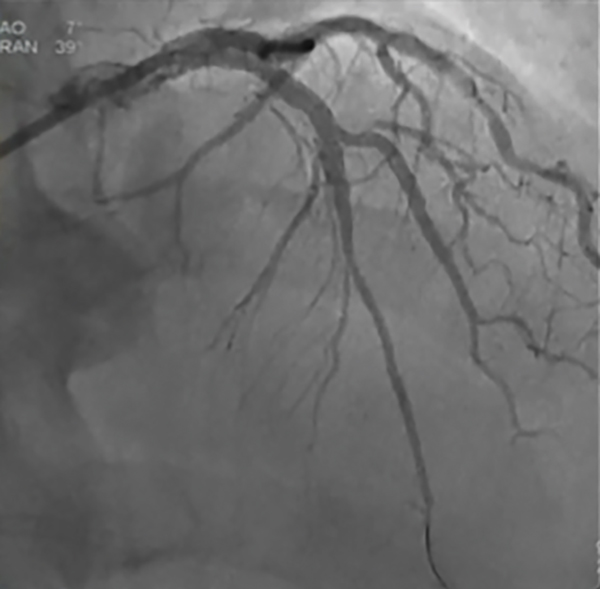

Diagnostic Angiogram

• Previous stents placed in the RCA and Circumflex are widely patent

• Disease in LAD and D1 unchanged from previous angiogram

• Severe vessel overlay and difficulty understanding healthy to healthy

landing zones (Figure 1)

Figure 1